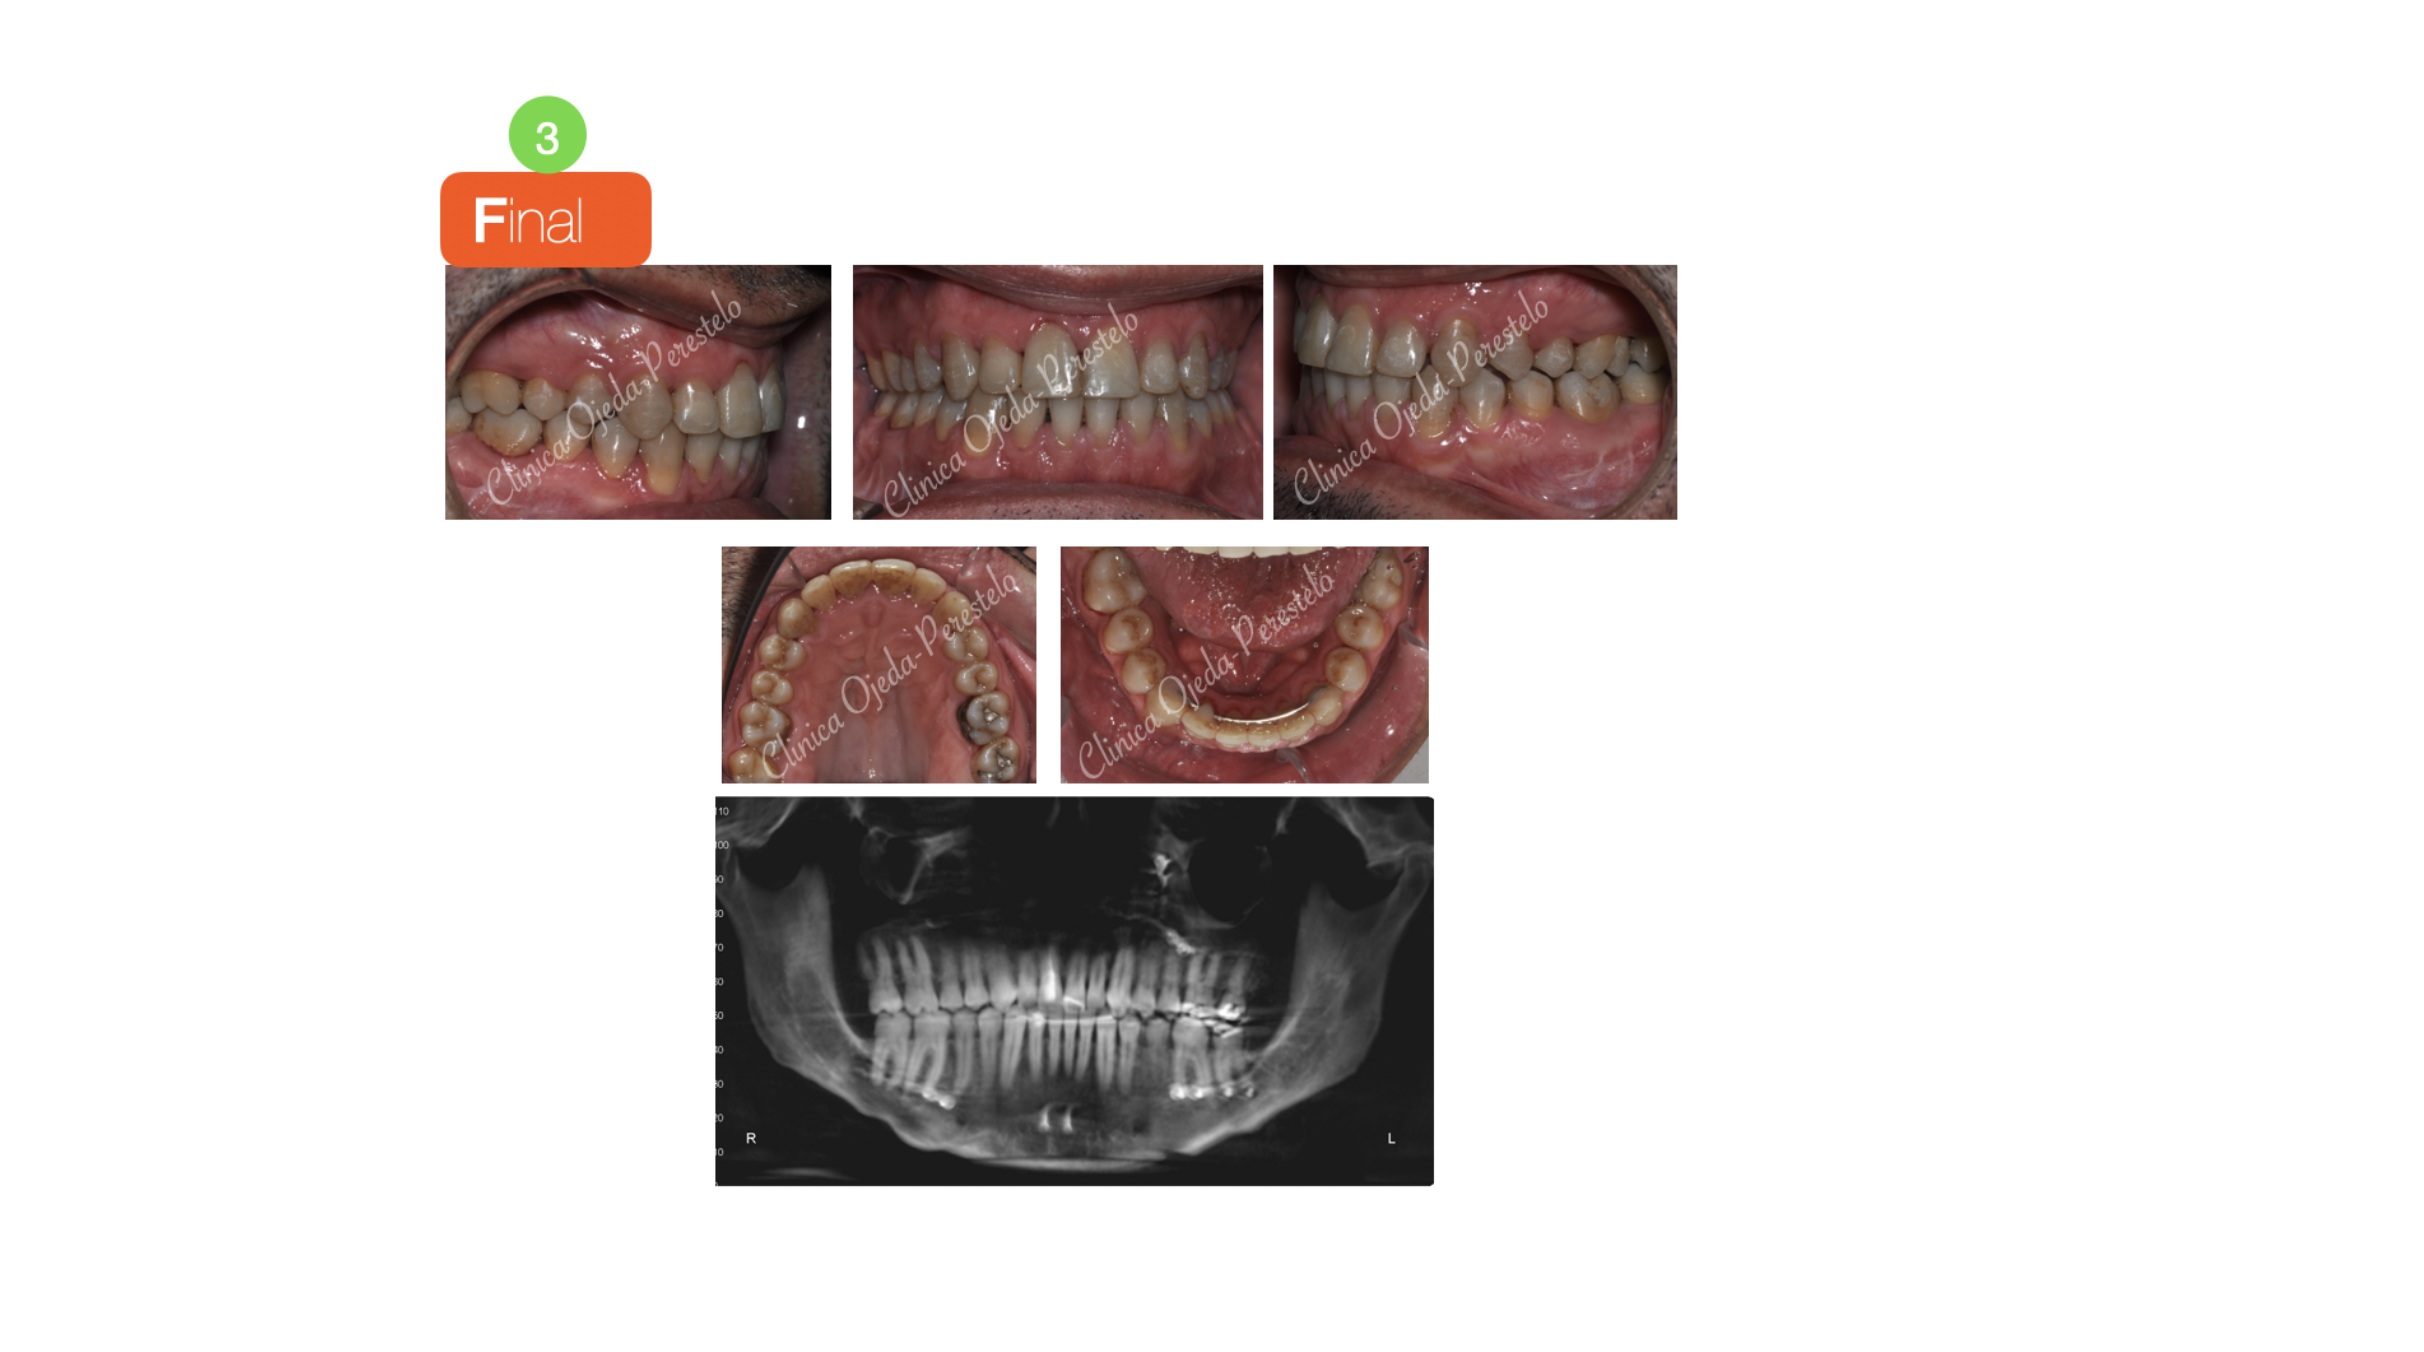

Biprotusión esquelética con Sonrisa Gingival

Paciente que consulta porque no le gusta su muy prominente sonrisa que le dificulta mantener la boca cerrada. El paciente quiere mejorar su aspecto facial así como el exceso de encías al sonreír (sonrisa gingival). Presenta un ordenamiento natural de sus piezas que nos permite comenzar con la intervención de Cirugía Ortognática desde un primer momento (Surgery First).

La intervención es realizada por el equipo del Dr Hdez-Alfaro y fue planificada con Lefort para Impactación y Retrusión del Maxilar conjuntamente con Osteotomia Sagital de Rama para centrado y retrusión Mandibular con Mentoplastia. Quisiera destacar la eliminación de la sonrisa gingival y la mejoría en la armonía facial y la permeabilidad de la vía Aérea.